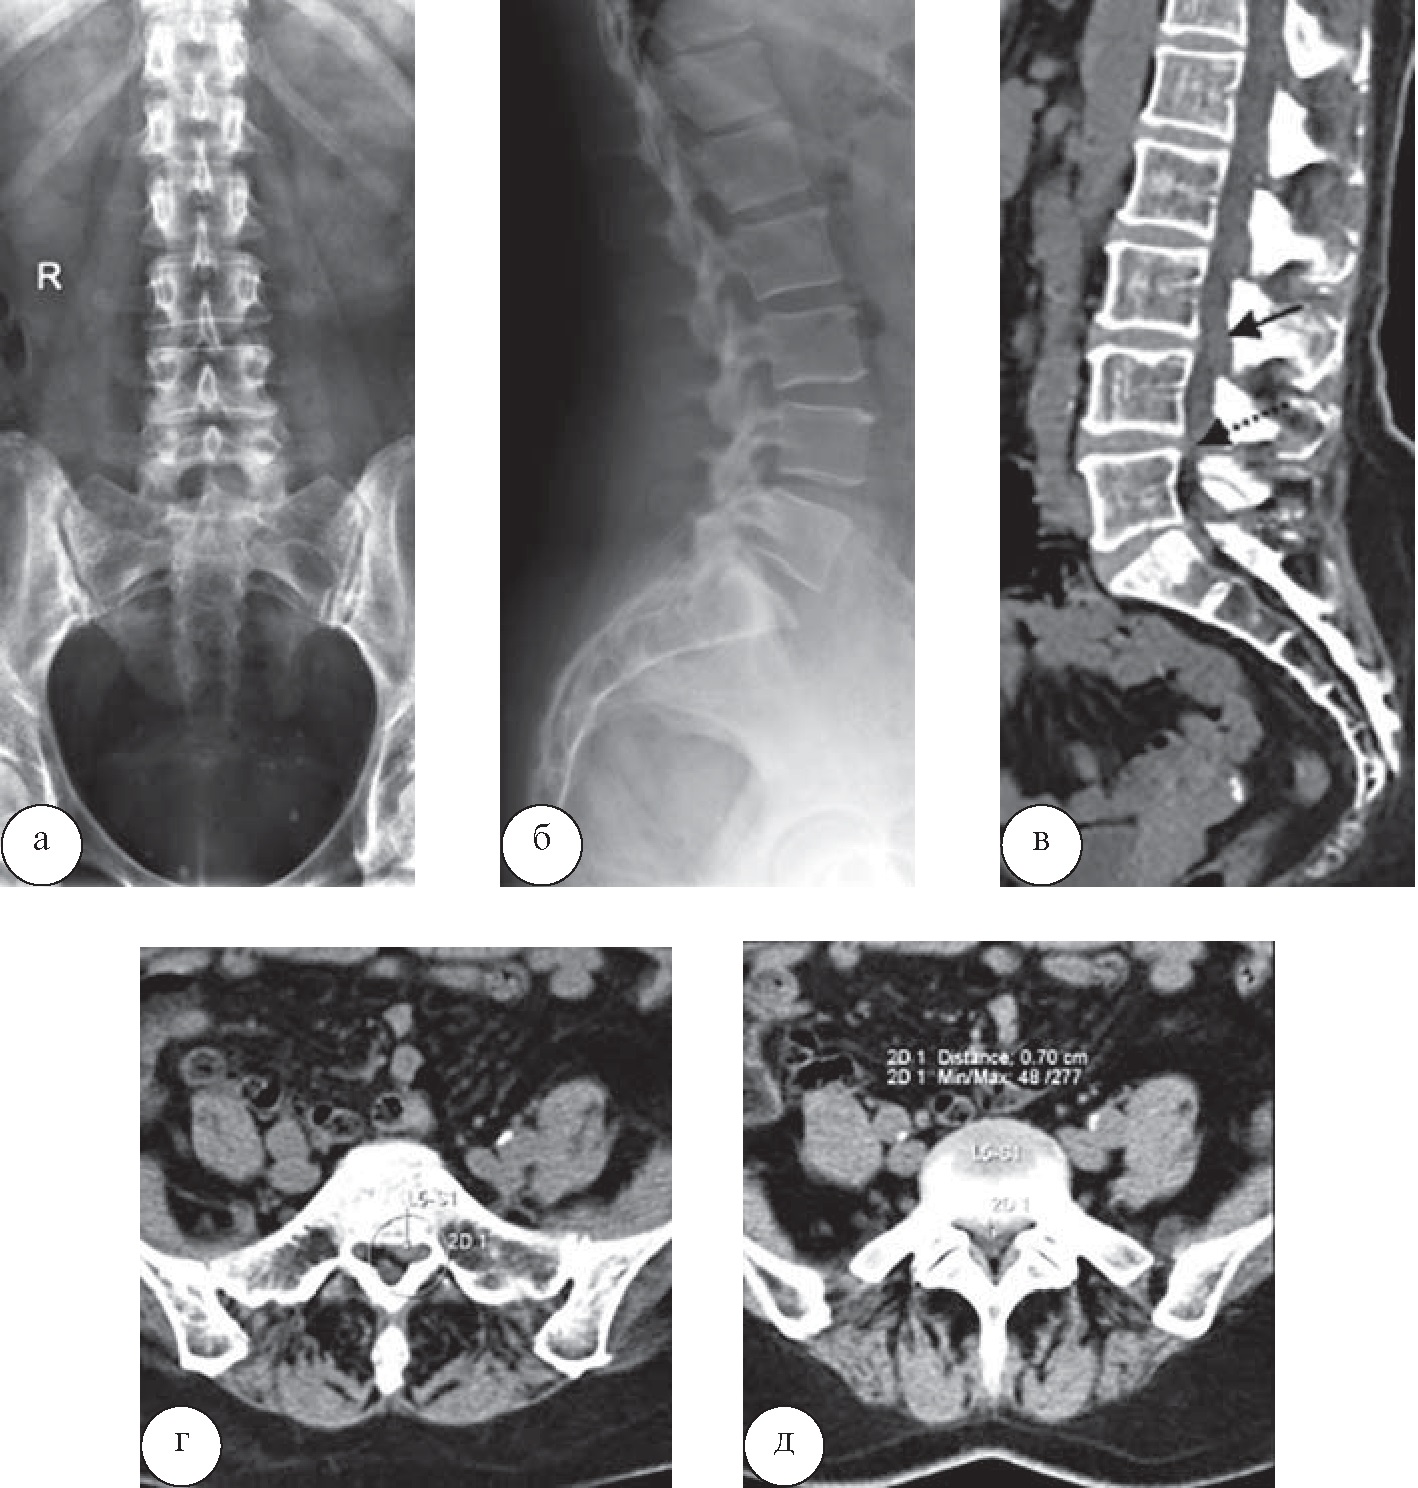

Ещё у одного пациента 67 лет в санаторной карте отсутствовало упоминание о раке предстательной железы в анамнезе, данные рентгенологического обследования представлены не были. Пациент был направлен на санаторное лечение в связи с выраженным болевым синдромом и диагнозом направления «остеохондроз позвоночника». Для уточнения причин болевого синдрома в санатории была выполнена КТ (рис. 8).

Рис. 8. Пациент Т., 67 лет. При КТ отмечаются множественные очаги уплотнения костной структуры в телах всех позвонков, остистых отростках, грудине и рёбрах. В анамнезе – брахитерапия по поводу рака предстательной железы, таким образом, данная картина соответствует остеобластическому метастатическому поражению скелета

По итогам КТ-обследования у данного пациента санаторное лечение было отменено в связи с наличием абсолютного противопоказания –множественных метастазов в кости. Таким образом, изменения программ лечебного воздействия в отношении всех пациентов были произведены после комплексного анализа данных КТ, МРТ, остеоденситометрии и рентгенографических исследований и получения дополнительной информации, отсутствовавшей в санаторных картах пациентов, заполненных на досанаторном этапе, вследствие детальной оценки дегенеративных изменений позвоночника. Наиболее значимую для врачей-специалистов санатория информацию дала КТ, поскольку при наличии протрузий и экструзий небольших размеров основными факторами, влияющими на выбор методик лечебного воздействия, служили изменения именно костных структур. Дополнительная информация, полученная при МРТ, имела значение в тех случаях, когда требовалось оценить степень сдавления нервных корешков либо спинного мозга, в то время как при КТ это не представлялось возможным. Однако результаты МРТ при этом значимо не повлияли на изменения программ лечения, запланированных в соответствии с результатами КТ, а явились дополнительным фактором, подтверждающим назначение или исключение конкретных методик лечебного воздействия из программы.